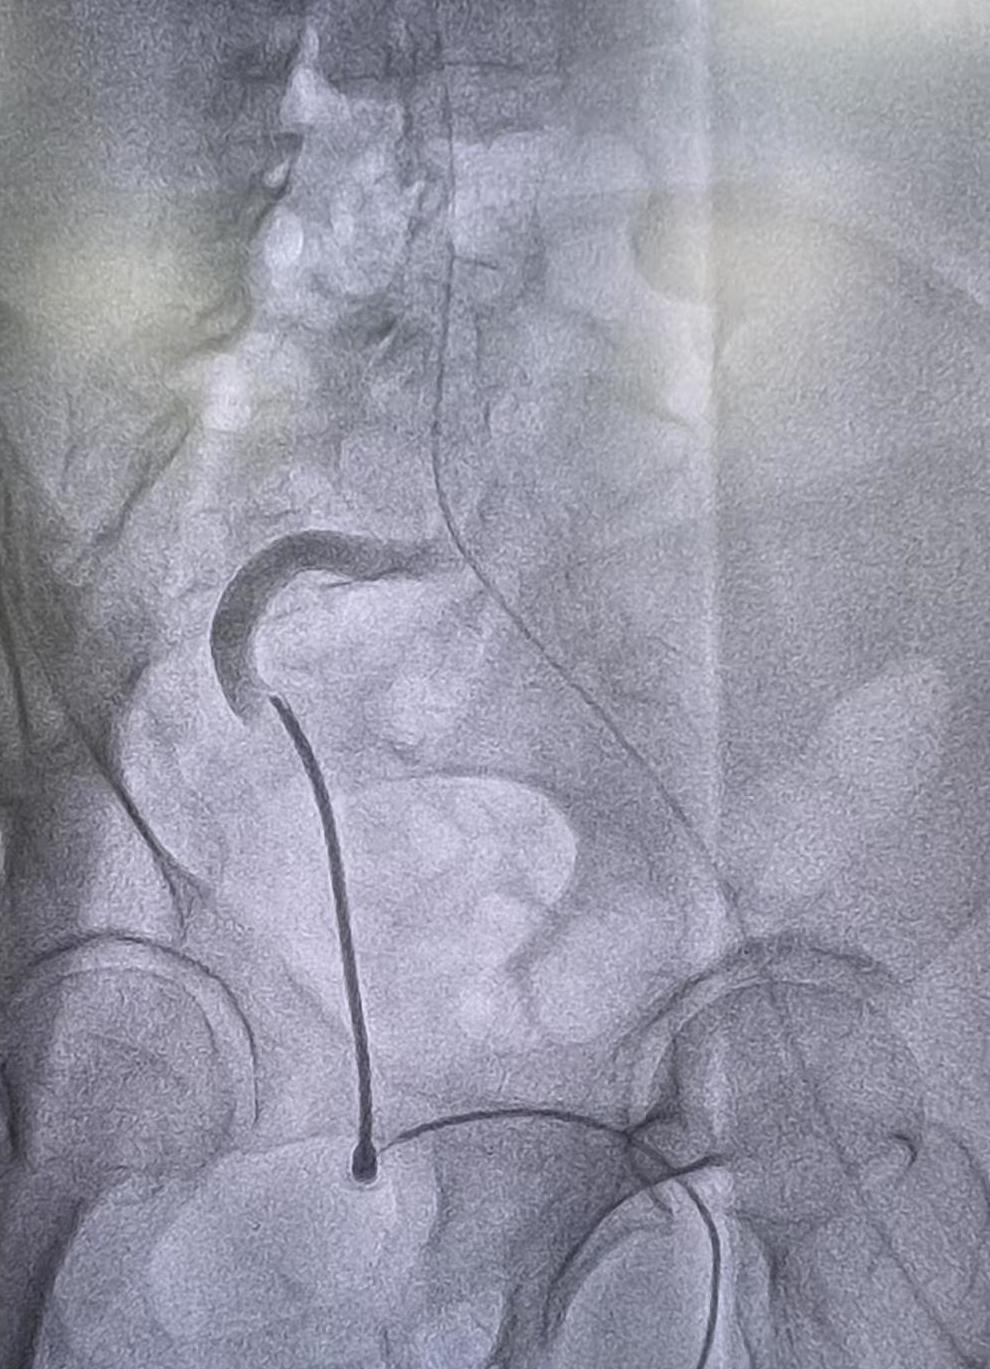

1.术前股动脉路径评估:

术前造影显示患者右侧股动脉走形极不规则,呈严重迂曲状(上图中显影的股动脉可见明显“S”形弯 曲)。如此扭曲狭窄的血管为经股入路送入器械带来了巨大挑战,稍有不慎导管鞘和输送系统可能无法 通过或导致血管损伤。针对这一情况,术者在股动脉预置了一根超硬度导丝,并通过逐级扩张血管入 口,谨慎地建立了能够容纳大直径鞘管的通路,为后续操作做好准备。